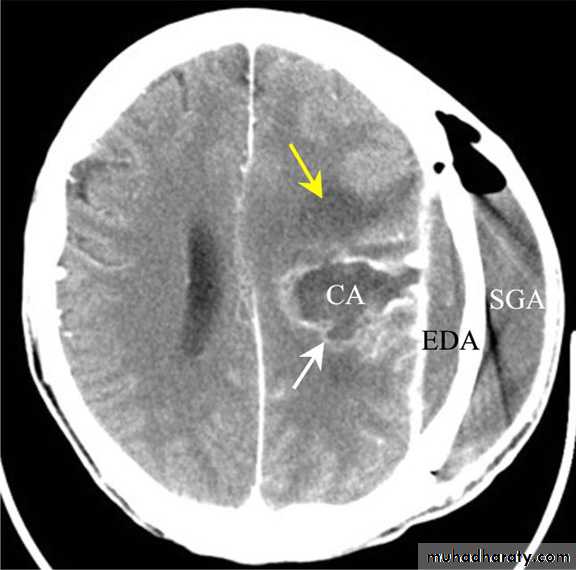

• B. Radiological Investigations:• CT or MRI is the investigation of choice.

• CT Brain is performed with and without contrast.

• They will show a single (or multiple) space occupying lesion that is well delineated with an enhancing wall, with variable surrounding oedema.

• B. Radiological Investigations:• The differential diagnosis of a single brain abscess in CT or MRI is a solitary metastasis, primary brain tumour or cerebral infarction.

• The differential diagnosis of multiple brain abscesses is from multiple metastasis and tuberculoma.